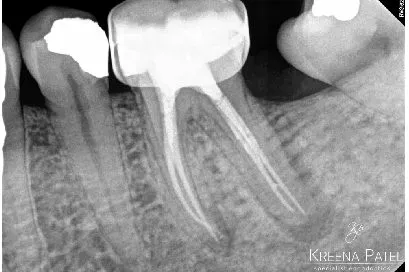

3. Phương pháp xác định WL

Chụp X-quang: Chóp hẹp được ước tính ngắn hơn từ 0.5 đến 1mm so với chóp x-quang. Tuy nhiên, vị trí và hình dạng của chóp hẹp có thể thay đổi, làm cho việc xác định chính xác bằng x-quang trở nên khó khăn.

Hai chiều: chụp X-quang là hình ảnh hai chiều và cung cấp góc nhìn hạn chế, đặc biệt là ở mặt phẳng má-lưỡi (Hình 4)

Nhiễu giải phẫu: giải phẫu chồng lên nhau có thể khiến việc hình dung khu vực quan tâm trở nên khó khăn (Hình 5)